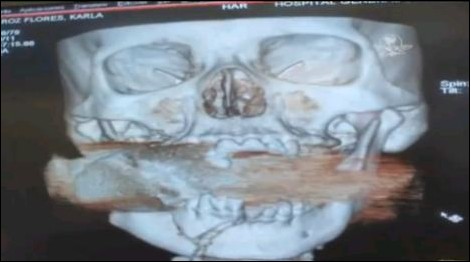

X光扫描图显示,一枚手榴弹卡在了弗洛雷斯的上下颌骨之间。

当弗洛雷斯醒来时,她已被送到了医院。医生们一开始还以为弗洛雷斯的脸部受到了石块的重击,但在进行X光扫描后发现,在她的上下颌骨之间卡着一枚未爆炸的手榴弹。有关专家判断,该手榴弹是经过发射器投掷的,一旦被引爆将会危及周围十米以内的人员。